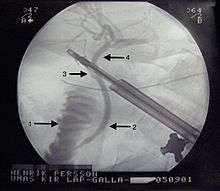

X-Ray during Laparoscopic Cholecystectomy. 1 - Duodenum. 2 - Common bile duct. 3 - Cystic duct. 4 - Hepatic duct.